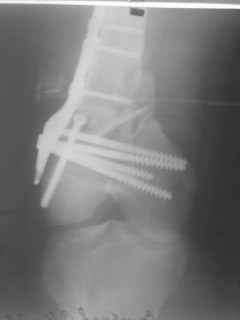

01.12.09г. оперировал больного с подобной травмой в ЦРБ на 4-е сутки после ДТП. Перелом открытый - рана находилась медиально чуть выше надколенника длиной примерно 3-4 см. До этого при поступлении было выполнено ПХО раны и скелетное вытяжение. На момент операции рана без признаков воспаления, состояние больного удовлетворительное.На первичных снимках перелом А3. На операции оказалось С3. Перелом фиксирован мыщелковой пластиной. Для репозиции понадобился медиальный доступ. Медиальный блок дополнен костно-губчатым аутотрансплантатом. На сегодняшний день раны заживают первично, швы еще не сняты, температура тела нормальная, отек бедра значительно уменьшился, имеется анемия средней степени, проводится ЛФК. Фото досылаю

Чем остеосинтез аппаратом в этом конкретном случае был бы предпочтительнее - и менее инвазивно, и пластику бы не надо было делать, и ось можно было бы лучше контролировать, включая послеоперационный период. А сейчас варусный коллапс градусов 15, и для исправления оси потребуется отдельная операция...

Снимки лучше бы делать на большем протяжении.